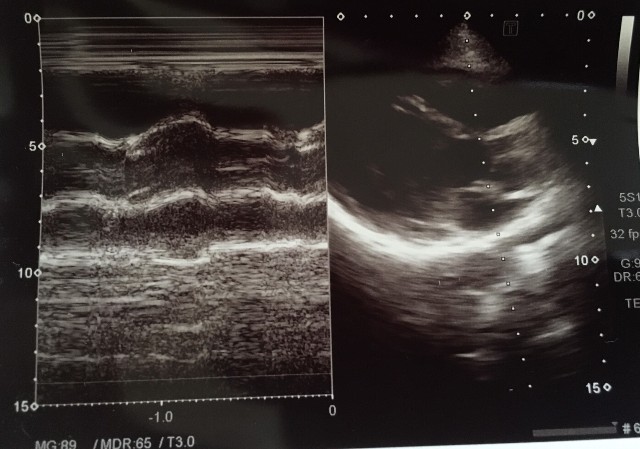

Mモード大動脈弁レベル

・大動脈弁基部を切る線で記録する

弁輪部にMモードのビームを合わせると、収縮期に右にずれてしまうのでややバルサルバ側に合わせる。

・腔に対して断面は垂直に入っているか?

・右室と大動脈と左房の大きさの関係は1:1:1

・大動脈弁の解放時に平行四辺形の線として描かれているか?box formation

・大動脈弁の開放径は1㎝以上あるか?1㎝未満だと弁の開放に障害がある。

Mモードの線が大動脈や左房の垂直に入ってないので少しプローブを右に倒す。

一肋間上からの描出を試してみる。

Mモードの大動脈前壁と大動脈後壁の動きが平行ではない

②

右室と左房がやや大きく見える。